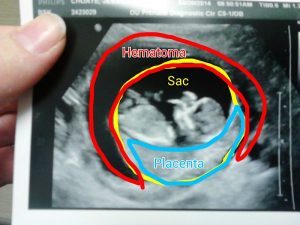

در طول حاملگی لخته خون بین لایه های جفت و رحم وجود دارد. دلیل آن به خوبی مشخص نیست. این وضعیت بیشتر برگشت ناپذیر است.این نوع خونریزی در حدود یک درصد از همه حاملگی اتفاق می افتد.چند دهه پیش، زمانی که یک زن سه ماهه اولیه بارداری دچار خونریزی میشد، پزشکانیک سقط جنین قریب الوقوع را احتمال میدادند و هیچ اطلاعات دیگری در این باره نداشتند. در حال حاضر با استفاده از سونوگرافی، پزشکان قادر به تشخیص قطعی تر هستند

در بعضی از خانم های حامله، لخته های خون ممکن است در داخل لایه های جفت تشکیل شده و تومور خونی زیرجفتی یا هماتوم را ایجاد کنند، در حقیقت همان خونی است که داخل لایه های کوریون جمع می شود. اگر لخته های خون بزرگ شوند، می توانند باعث جداشدن لایه های جفتی و دیواره رحم شوند. البته بیشتر تومورهای خونی زیرجفتی، در هفته بیستم دوره بارداری، خودشان را بدون هیچ عمل جراحی، درمان می کنند. علائم و نشانه هایی برای این بیماری وجود دارد که می توانید در هفته های اول حاملگی، آنها را تشخیص دهید.

?3-با سونوگرافی می توان وجود این تومور را مشخص کرد. سونوگرافی ممکن است از شکم و بر روی شکم و یا به صورت ترانس واژینال، از طریق مهبل انجام بگیرد. در بعضی از موارد، تشخیص این تومور دشوار می شود. البته اگر خونریزی وجود داشته باشد و دکتر بتواند سلامت جنین را از طریق سونوگرافی تشخیص دهد، می تواند وجود این تومور را نیز تشخیص دهد. در بعضی مواقع نیز، دکتر در پی سونوگرافی مرتب بیمار، بدون اینکه خود بیمار علائمی را دیده باشد، این تومور را تشخیص می دهد.